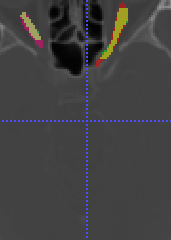

In Chapter 6, we propose an end-to-end, atlas-free 3D convolutional deep learning framework for fast and fully automated whole-volume HaN anatomy segmentation [115]. Our deep learning model, called AnatomyNet, segments OARs from head and neck CT images in an end-to-end fashion, receiving whole-volume HaN CT images as input and generating masks of all OARs of interest in one shot. AnatomyNet is built upon the popular 3D U-net architecture, but extends it in three important ways: 1) a new encoding scheme to allow auto-segmentation on whole-volume CT images instead of local patches or subsets of slices, 2) incorporating 3D squeeze-and-excitation residual blocks in encoding layers for better feature representation, and 3) a new loss function combining Dice scores and focal loss to facilitate the training of the neural model. These features are designed to address two main challenges in deep-learning-based HaN segmentation: a) segmenting small anatomies (i.e., optic chiasm and optic nerves) occupying only a few slices, and b) training with inconsistent data annotations with missing ground truth for some anatomical structures. We collect 261 HaN CT images to train AnatomyNet, and use MICCAI Head and Neck Auto Segmentation Challenge 2015 as a benchmark dataset to evaluate the performance of AnatomyNet. The objective is to segment nine anatomies: brain stem, chiasm, mandible, optic nerve left, optic nerve right, parotid gland left, parotid gland right, submandibular gland left, and submandibular gland right. Compared to previous state-of-the-art results from the MICCAI 2015 competition, AnatomyNet increases Dice similarity coefficient by 3.3% on average. AnatomyNet takes about 0.12 seconds to fully segment a head and neck CT image of dimension , significantly faster than previous methods. In addition, the model is able to process whole-volume CT images and delineate all OARs in one pass, requiring little pre- or post-processing. We demonstrate that our proposed model can improve segmentation accuracy and simplify the auto-segmentation pipeline. These contributions are released as an open-source software package called AnatomyNet, which is publicly available555https://github.com/wentaozhu/AnatomyNet-for-anatomical-segmentation. Portions of this chapter were published as part of [115].